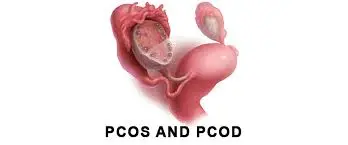

कारण 2: PCOD और PCOS – आज की सबसे आम समस्या

आज के समय में PCOD और PCOS महिलाओं में तेजी से बढ़ रही समस्याएं हैं। इन स्थितियों में ओवरी ठीक से काम नहीं कर पाती, जिससे ओव्यूलेशन अनियमित हो जाता है। जब लंबे समय तक ओव्यूलेशन नहीं होता, तब गर्भाशय की परत लगातार मोटी होती जाती है।

यह भी पढ़ें: PCOD और PCOS: आसान भाषा में क्या हैं, कारण, लक्षण और इलाज

जब आखिरकार पीरियड आता है, तो वह बहुत ज्यादा ब्लीडिंग के साथ आता है। कई बार यह ब्लीडिंग 8–10 दिनों तक भी चल सकती है। इसके साथ वजन बढ़ना, चेहरे पर बाल आना, मुंहासे और पीरियड्स का अनियमित होना भी आम लक्षण होते हैं।

PCOS से जुड़ी ब्लीडिंग को नजरअंदाज करना भविष्य में फर्टिलिटी से जुड़ी समस्याओं को जन्म दे सकता है।